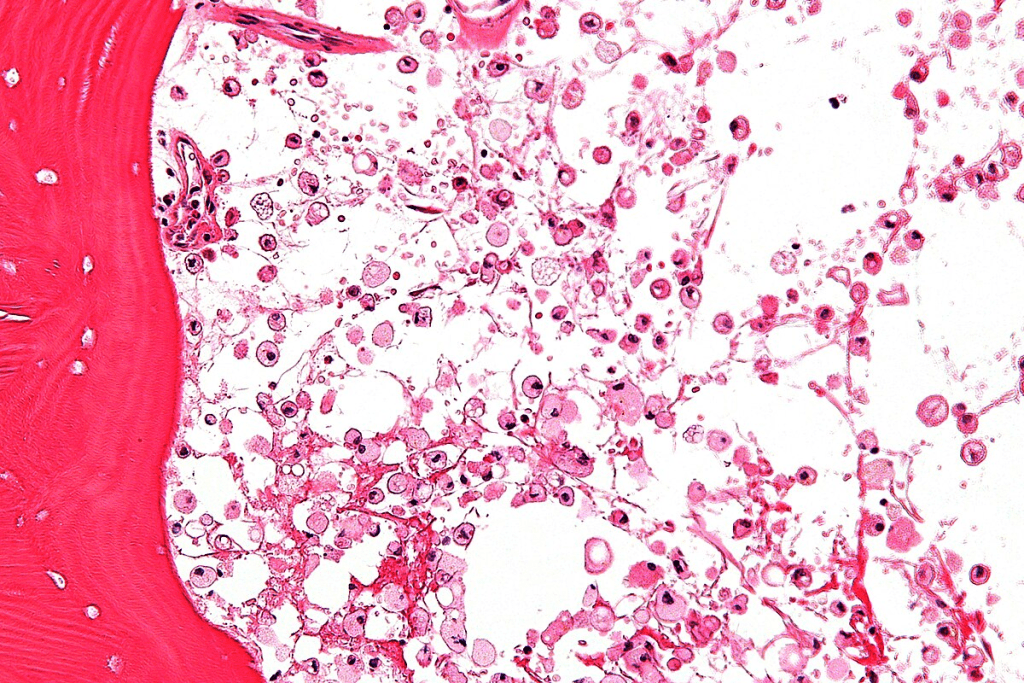

Normal vs. Abnormal Red Blood Cell Morphology

Normal red blood cells are all about the same size and shape, around 7-8 micrometers. But, in microcytic anemia, cells are much smaller.

Here’s how normal and abnormal red blood cells differ:

| Characteristics | Normal RBC | Microcytic RBC |

| Size | 7-8 micrometers | Less than 7 micrometers |

| Hemoglobin Content | Normal | Reduced |

Knowing these differences is vital for diagnosing and treating microcytic anemia well.